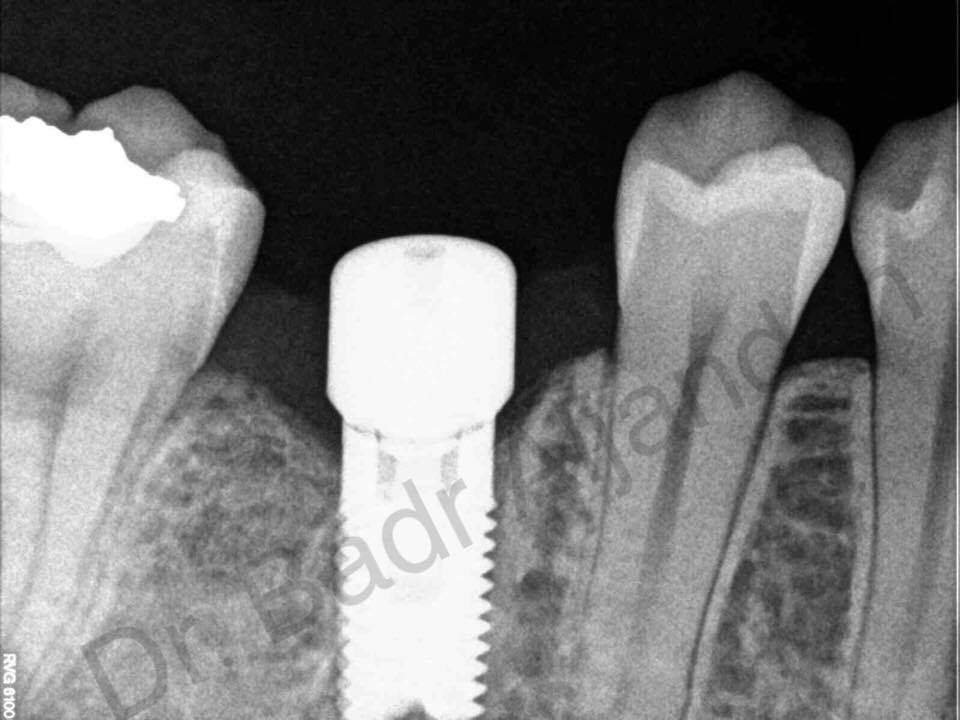

غرسات الأسنان مصنوعة من مادة التيتانيوم. توضع داخل عظام الفك في نفس مكان الأسنان المفقودة. الجزء المعدني الموجود داخل عظام الفك يعمل كوتد بديلا لجذر الأسنان. يتم تركيب الجزء المعدني بواسطة عملية جراحية داخل الفك. وبعد فترة يتم ترابط عظام الفك مع الجزء التيتانيوم مسببا تثبيت قوي للجزء الصناعي داخل الفك. الجزء الأوسط يثبت وتد قوي للأسنان الصناعية.

مراحل تركيب الغرسات (الزرعات) من الأوتاد إلى الأسنان الصناعية